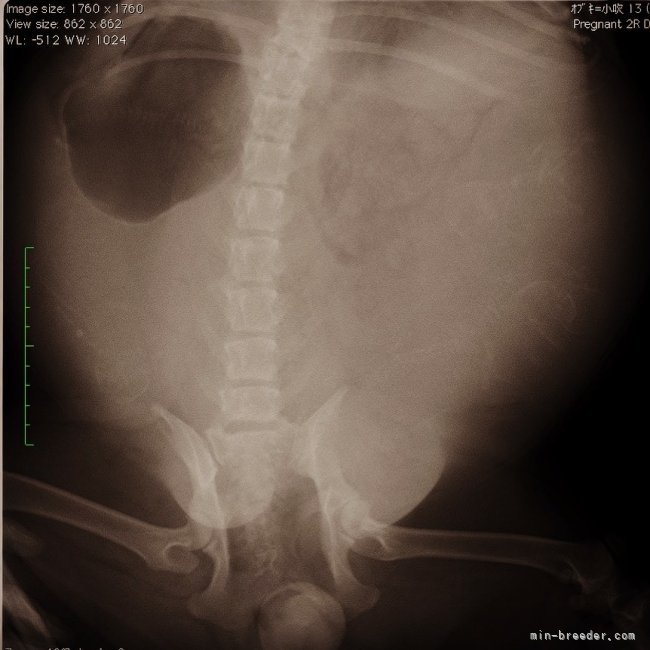

出産予定日まで4日🤭何頭かなぁ〜?出産予定日まで4日‼︎ てんちゃんレントゲン🩻撮影しました❣️ 5頭かなぁ〜? ...

レントゲン撮影をしました🐶🐶🐶🐶…出産予定日まで11日☺️❣️ 本日、頭数確認のためレントゲン写真を撮ったのですが、あ...

お腹の子犬は3頭‥?4頭‥?5頭‥?6頭‥?笑😁♥️本日はエコー検査とレントゲン検査😊💓 元気元気〜 子犬わかますかー? お腹の...